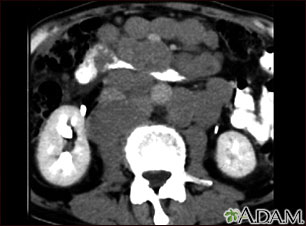

- Tomografía computarizada del tórax, el abdomen y la pelvis